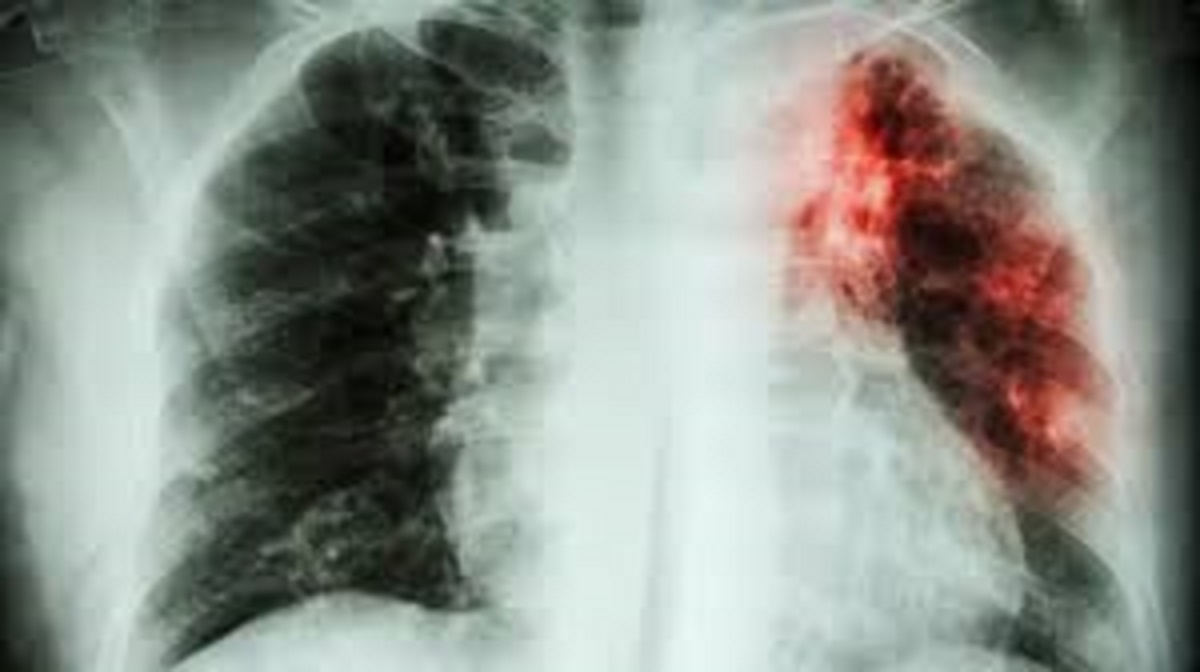

विश्व स्वास्थ्य संगठन ने ‘विश्व तपेदिक रिपोर्ट 2023’ जारी की है। जिसके अनुसार दुनिया की कुल टीबी रोगियों की संख्या में से 27 प्रतिशत भारत में मौजूद है। 2025 तक भारत से तपेदिक (टीबी) को खत्म करने के लिए भारत सरकार द्वारा कई पहल की जा रही हैं। तपेदिक के निदान के लिए बड़ी संख्या में परीक्षण किए जा रहे हैं और उपचार की उपलब्धता बढ़ा दी गई है। हालाँकि वैश्विक लक्ष्य 2030 तक पूरी दुनिया से तपेदिक को ख़त्म करने का रखा गया है, लेकिन भारत ने इस लक्ष्य को पाँच साल पहले ही हासिल करने का लक्ष्य रखा है। हालाँकि भारत अभी भी तपेदिक जैसे जीवाणु संक्रमण से होने वाली बीमारियों की सबसे अधिक घटनाओं का सामना कर रहा है।

2022 में भारत में 28.2 लाख लोग तपेदिक से प्रभावित होंगे। WHO की रिपोर्ट के मुताबिक, यह डेटा बताता है कि भारत में हर 11 सेकंड में एक व्यक्ति तपेदिक से संक्रमित होता है। भारत में वैश्विक रोगी आबादी का 27 प्रतिशत हिस्सा है। 2022 की तुलना में मरीजों की संख्या में एक फीसदी (पहले 28 फीसदी) की कमी आई है। सबसे महत्वपूर्ण बात यह है कि मरीजों के पंजीकरण में उल्लेखनीय वृद्धि हुई है जो एक सकारात्मक बात है। तपेदिक के लिए भारत की उच्च पहचान रणनीतियों के कारण 2022 में 24.22 लाख टीबी के मामलों की अब तक की सबसे अधिक संख्या दर्ज की गई। रिपोर्ट के अनुसार, यह संख्या कोरोना काल से पहले से भी ज्यादा है। साल 2019 में भारत में तपेदिक मरीजों की संख्या 24.04 दर्ज की गई। विशेष रूप से इंडोनेशिया और फिलीपींस सहित दुनिया भर के देशों में टीबी रोगियों के पंजीकरण में 67 प्रतिशत की गिरावट देखी गई है। हालांकि, रिपोर्ट में यह भी कहा गया है कि भारत ने मरीजों का ठीक से रजिस्ट्रेशन किया है।

भारत ने 2025 तक भारत से तपेदिक को ख़त्म करने का लक्ष्य रखा है। राष्ट्रीय रणनीतिक योजना के अनुसार, 2017 से 2025 तक टीबी के मामलों की संख्या को प्रति 1 लाख जनसंख्या पर 44 तक लाने का लक्ष्य था। विश्व क्षय रोग रिपोर्ट 2023 के अनुसार वर्तमान में यह संख्या प्रति लाख 199 है। ऐसे में भारत द्वारा निर्धारित लक्ष्य को हासिल करना एक बड़ी चुनौती होने वाली है। पहले यह तय किया गया था कि 2023 तक प्रति लाख आबादी पर मरीजों की संख्या घटाकर 77 कर दी जाएगी।